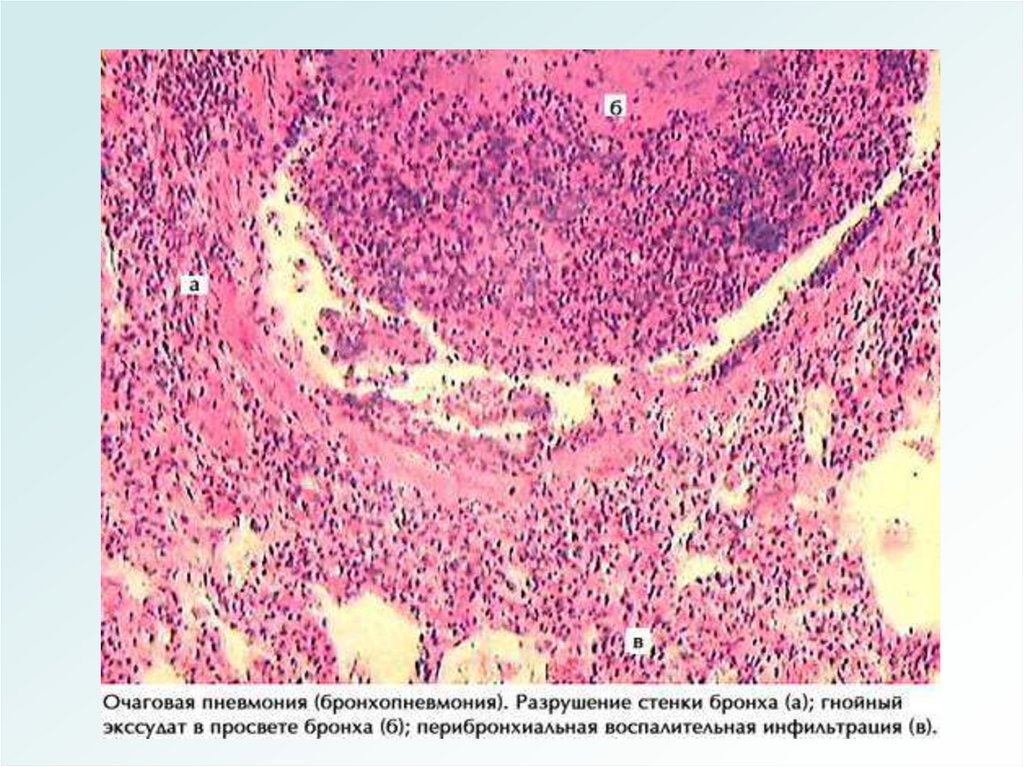

Бронхопневмония (очаговая)

• Составляет 62-70% острых пневмоний.

• Чаще - вторичная, самостоятельным

заболеванием является только у детей

раннего возраста и лиц пожилого и

старческого возраста.

• Полиэтиологична.

• Возникает на фоне снижения иммунитета.

МОРФОЛОГИЯ

БРОНХОПНЕВМОНИИ

1.Очаговое воспаление (бронхиолит +

альвеолит)

2.Эмфизема

3.Ателектаз